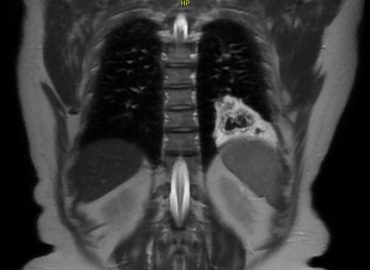

Embarazo de 26,2 semanas. MC Genitorragia